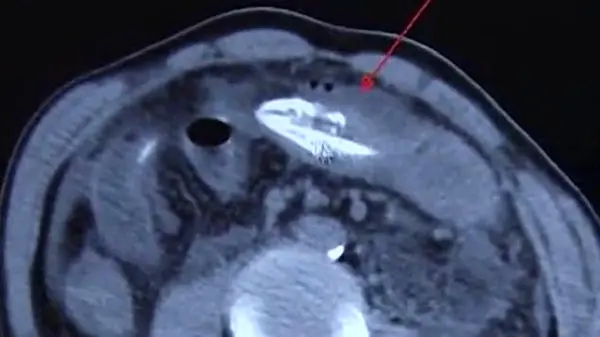

به گزارش گروه ترجمه رکنا، سی تی اسکن مرد میانسال چینی پزشکان بیمارستان را به وحشت انداخت.

بنا به گزارش رسانه های خارجی، پزشکان با انجام آزمایشات متوجه شدند که یک مار ماهی مرده 16 اینچی در معده بیمار وجود دارد که موجب بیماری او و دل دردش شده است.

پزشکان جراح پس از یک عمل جراحی موفق به خارج کردن این جانور از معده این بیمار 50 ساله شدند و بنا به گفته پزشکان بخش‌هایی از معده این بیمار شدیدا عفونت کرده بود و به همین خاطر او با دل درد شدید به بیمارستان مراجعه کرد.